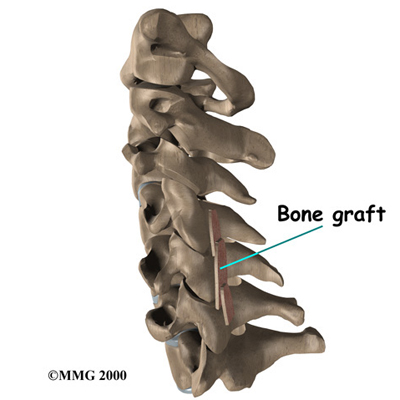

Cervical Fusion

A fusion surgery joins two or more bones into one solid bone. The purpose for doing spinal fusion is to increase the space between the vertebrae and to keep the sore joint from moving. This is usually done by placing a small block of bone graft in the space where a disc was removed. Opening up more space enlarges the neural foramen, takes pressure off the nerve roots, and eases tension on the facet joints. Cervical fusion is used to treat neck problems such as cervical radiculopathy, disc herniations, fractures, and spinal instability. There are two main types of fusion for neck problems.

- Anterior Discectomy and Fusion: Anterior discectomy and fusion is done through the front of the neck. After taking out the disc (discectomy), the disc space is filled with a small graft of bone. The bone is allowed to heal, fusing the two vertebrae into one solid bone.

Small Graft of Bone

-

Related Document: FYZICAL Middleburg's Guide to Anterior Cervical Discectomy and Fusion

- Posterior Fusion: In posterior fusion, the surgeon lays small grafts of bone over the back of the spine. When these bones heal together, they fuse the two vertebrae into one solid bone. Posterior fusions in the cervical spine are primarily used to treat fractures of the neck.

Posterior Fusions

-

Related Document: FYZICAL Middleburg's Guide to Posterior Cervical Fusion

The bone graft needs time to heal in order for the fusion to succeed. This requires the neck to be held still. After cervical fusion surgery, patients usually have to wear a special neck brace for several months. These neck braces are often bulky and restrictive. Recently, surgeons have begun using metal plates and screws (often referred to as instrumentation) to lock the bones in place. The instrumentation is fastened to the vertebrae, where it holds the bones still while the graft heals.

Locking the Bones in Place